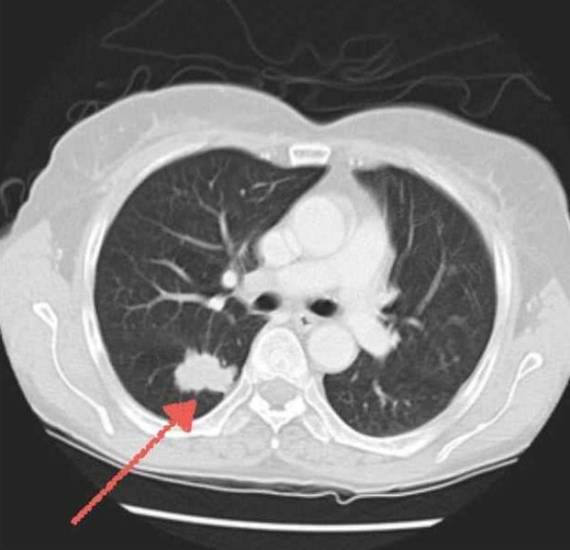

Высокодифференцированная аденокарцинома легкого

Факторы, которые провоцируют формирование этого вида рака, следующие:

- Активное или пассивное курение;

- Частое вдыхание канцерогенов (вредное производство);

- Хронические застарелые болезни легких.

Одним из характерных признаков заболевания считается кашель с отхаркиванием большого количества мокроты слизистой консистенции. Опухоль может быть как ацинарной, так и папиллярной (сосочковой) формы. В первом случае это рак с железистой структурой и крупными клетками, во втором – с многоядерной выстилкой. Обе формы склонны к усиленному слизеобразованию.

На более поздних этапах развития этот вид рака проявляется натужным кашлем, повышением температуры, больной чувствует нехватку воздуха и страдает одышкой даже в спокойном состоянии.